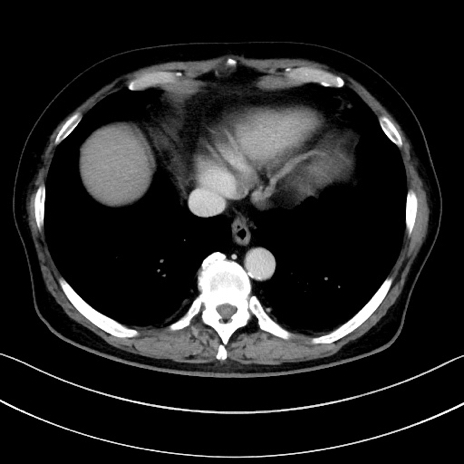

冠状断像

【症例】70歳代男性

【主訴】腹痛

【現病歴】今朝から腹痛あり。全体的に痛い。特に左上の方。排ガスが今日はない。冷や汗が出る。

【既往歴】直腸癌術後

【身体所見】左側腹部〜上腹部に圧痛あり。腹膜刺激症状明らかなではない。軽度反跳痛。左下腹部に術後瘢痕あり。

【データ】WBC 7700、CRP 0.02